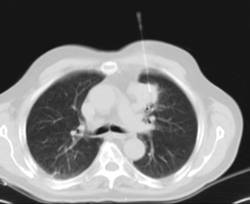

- Tórax- TC Tórax Prueba diagnóstica que consiste en obtener imágenes del tórax de alta definición anatómica (pulmones, corazón, mediastino, grandes vasos, caja torácica, etc.) mediante el empleo de un equipo de TC (Tomografía Computarizada). Dichas imágenes se estudian posteriormente en una estación de trabajo que permite reconstrucciones bidimendionales en diferentes planos del espacio y también reconstrucciones 3D (volumétricas). Algunos estudios requieren el empleo de contraste yodado para mejorar la definición de las imágenes. Prueba diagnóstica que consiste en obtener imágenes del tórax de alta definición anatómica (pulmones, corazón, mediastino, grandes vasos, caja torácica, etc.) mediante el empleo de un equipo de TC (Tomografía Computarizada). Dichas imágenes se estudian posteriormente en una estación de trabajo que permite reconstrucciones bidimendionales en diferentes planos del espacio y también reconstrucciones 3D (volumétricas). Algunos estudios requieren el empleo de contraste yodado para mejorar la definición de las imágenes.

- TC Tórax alta resolución Prueba diagnóstica que consiste en el estudio del pulmón mediante el empleo de un equipo de TC (Tomografía Computarizada) obteniendo imágenes bi y tridimensionales que permiten un estudio anatómico altamente específico del pulmón, pudiendo valorar estructuras anatómicas de tamaño muy pequeño. Es una técnica muy importante en el estudio de los pacientes con sospecha de enfermedad pulmonar. Prueba diagnóstica que consiste en el estudio del pulmón mediante el empleo de un equipo de TC (Tomografía Computarizada) obteniendo imágenes bi y tridimensionales que permiten un estudio anatómico altamente específico del pulmón, pudiendo valorar estructuras anatómicas de tamaño muy pequeño. Es una técnica muy importante en el estudio de los pacientes con sospecha de enfermedad pulmonar.